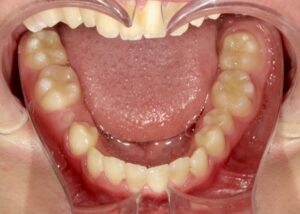

下顎

- Before